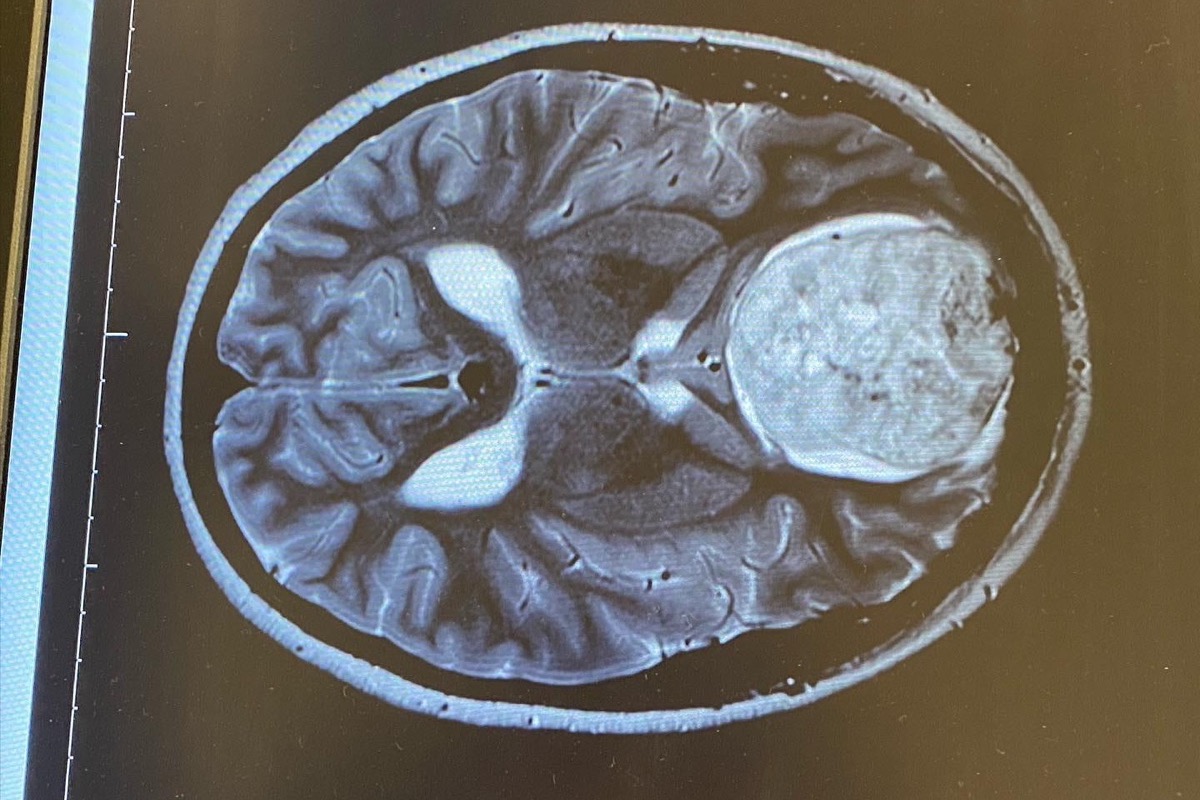

Ashlee will have to undergo a very dangerous brain surgery due to this brain tumor that has been growing for years and just recently a doctor has caught it. She refuses to ask for money so I took it upon my self to start this go fund me, she will be out of work for 3 months at least and although she has amazing support through her family, they do not have the funds to be able to pay her bills. She has an almost 4 year old boy she also need to support. Anything will help. And if you cannot donate, please send thoughts/prayers/hope, however you choose to manifest positivity.